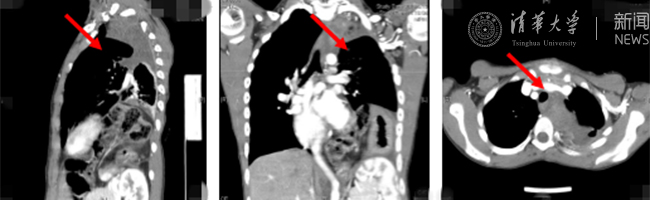

8xbet(中国)网8月30日电(通讯员 杨峰)如图中所示,本是正常人心脏、左肺的位置,被发于神经鞘的巨大肿瘤占据,导致一位刚满12岁的男孩胸痛、咳嗽、呼吸困难。近日,北京清华长庚医院神经外科与胸外科联手,由神经外科王贵怀主任主刀,成功为男孩切除胸腔巨大神经鞘肿瘤。

患者胸腔内巨大的肿瘤。

半年前,患者经常会出现胸痛、咳嗽和呼吸困难,在当地医院检查发现左侧胸腔巨大占位,左肺及心脏明显受压。王贵怀大夫接诊,仔细查体了解病情,并反复认真阅片后,认为左侧胸腔巨大肿瘤来自于胸椎椎管内,神经鞘瘤可能性大。该肿瘤体积巨大,占据绝大部分胸腔空间,压迫左肺、纵隔大血管及膈肌。